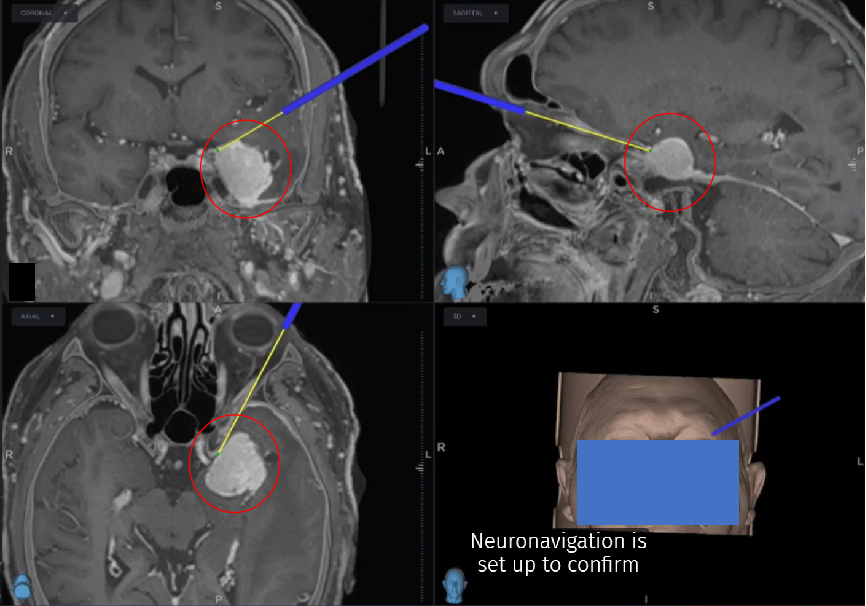

综合考虑到肿瘤内没有包绕血管,患者秃顶且眉毛浓密,决定采用经眶入路——transorbital eyebrow lacrimal keyhole approach(TELKA),即从眉弓切除这个肿瘤。该入路可提供更好的手术视野和足够的操作空间,减少眼球的危险牵拉。为显微镜和内镜的使用提供了十分出色的可视化和可操作性。

显微镜+神经内镜“双镜联合”手术,神经导航精准定位,“筷子技术”发挥优势。

- 神经导航定位

术后CT扫描显示肿瘤全切,无手术并发症。患者未出现任何神经功能缺损。术后第6天拆线出院。